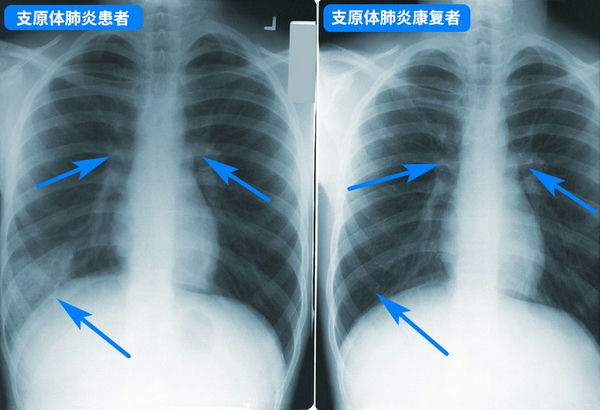

支原体肺炎胸透片

支原体肺炎***般并不严重,但要小心预防病情加重,尽早就医,如持续发烧5天以上、剧烈咳嗽不止,则***定要就医,以评估肺部是否受影响,以及是否存在并发症。儿童支原体肺炎***般用阿奇霉素等大环内酯类药物,但因为亚洲地区滥用药物引起的耐药性问题,很可能效果不佳,需要中途换药,具体应该遵医嘱。